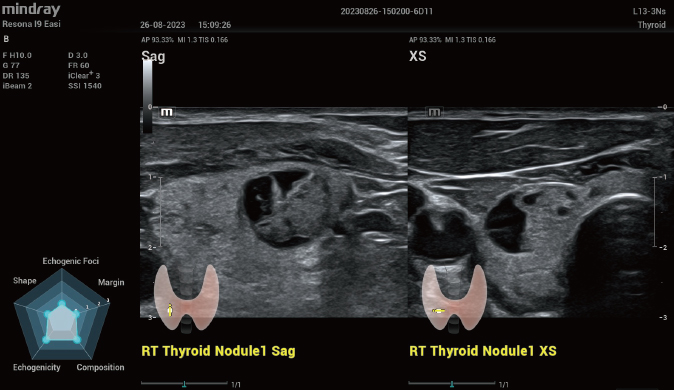

Für die Ultraschalltechnologie stellt die ZST+-Plattform einen bedeutenden Fortschritt dar, da sie statt der herkömmlichen Strahlformung die Kanaldatenverarbeitung verwendet. Diese bahnbrechende Innovation löst übliche Zielkonflikte zwischen räumlicher Auflösung, zeitlicher Auflösung und Homogenität des Gewebes auf, woraus sich eine beispiellose Bildqualität ergibt, die den Weg frei macht für unendlich viele Bildgebungslösungen.

Das Resona I8 weist vielfältige klinische Lösungen auf, die speziell für den jeweiligen Anwendungsbereich entwickelt wurden. Die Technologie baut auf einem tiefgreifenden Verständnis verschiedener klinischer Szenarien auf und bietet eine umfassende Serie fortschrittlicher Diagnoseinstrumente, beispiellose Intelligenz und präzise Analysen zur Verbesserung von Diagnosesicherheit, Qualitätskontrolle und Scaneffizienz.